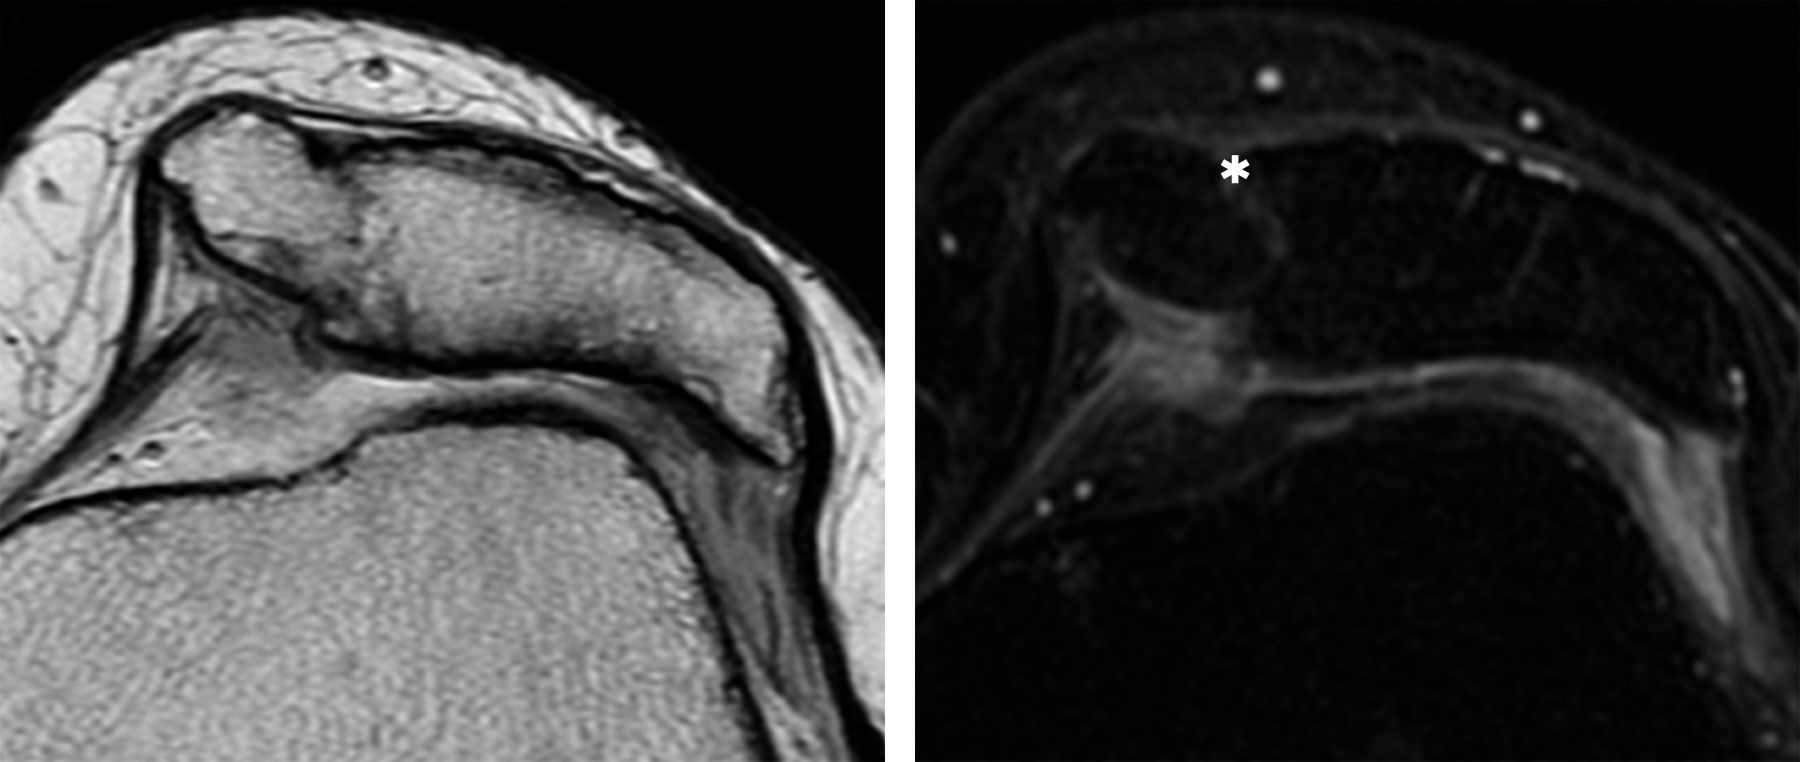

Patellar duplication is a rare entity, where a patella and an accessory patella develop from two ossification nuclei. This pathology can present with a variety of clinical problems depending on its stability. It is considered stable when there is soft tissue between the bone segments allowing little movement thereof. The most important pathology as a differential diagnosis is the bipartite patella, its main difference is that in the bipartite patella the fragments are joined by the continuous covering of the articular cartilage, and no extra ligamentous structures are observed.